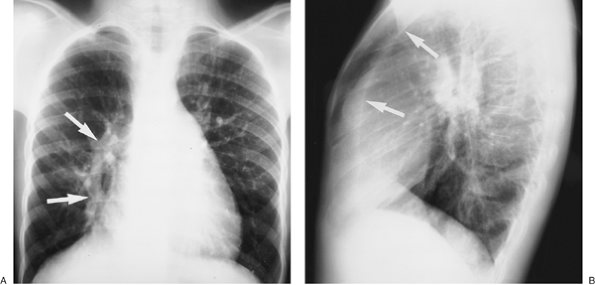

FIGURE 16-6. Pulmonary venolobar syndrome. A: PA chest radiograph of an 11-year-old girl shows a curvilinear band of opacification (arrows) adjacent to the right heart border, representing an anomalous pulmonary vein draining into the inferior vena cava. The vein is shaped like a Turkish sword, giving rise to the name "scimitar syndrome," another term used to describe this entity. Hypoplasia of the right lung is not clearly seen on this view. B: Lateral view shows a retrosternal band of opacification (arrows), created by shortening of the anteroposterior diameter of the right lung, and contact of the anterior right lung with a rotated and shifted mediastinum.